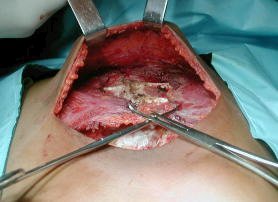

Intervención quirúrgica

• Ténica Ravicht modificada:

• Incisión sub-mamaria transversa.

• Disección muscular de ambos pectorales, permite la exposición de la pared costal costal anterior, desde el manubrio hasta el sifoides.

• Desperiostización y resección de III arco al X arcos cartilaginosos bilaterales.

• No fue necesario condroplastia del los segundos arcos costales.

• Dos osteotomias transversas fueron necesarias para corregir la deformidad esternal, se fijan mediante sutura alambre No.5 puntos X.

• La resección del sifoides se realiza a continuación.

• Se fijan los pectorales y se reinserta el recto anterior del abdomen.